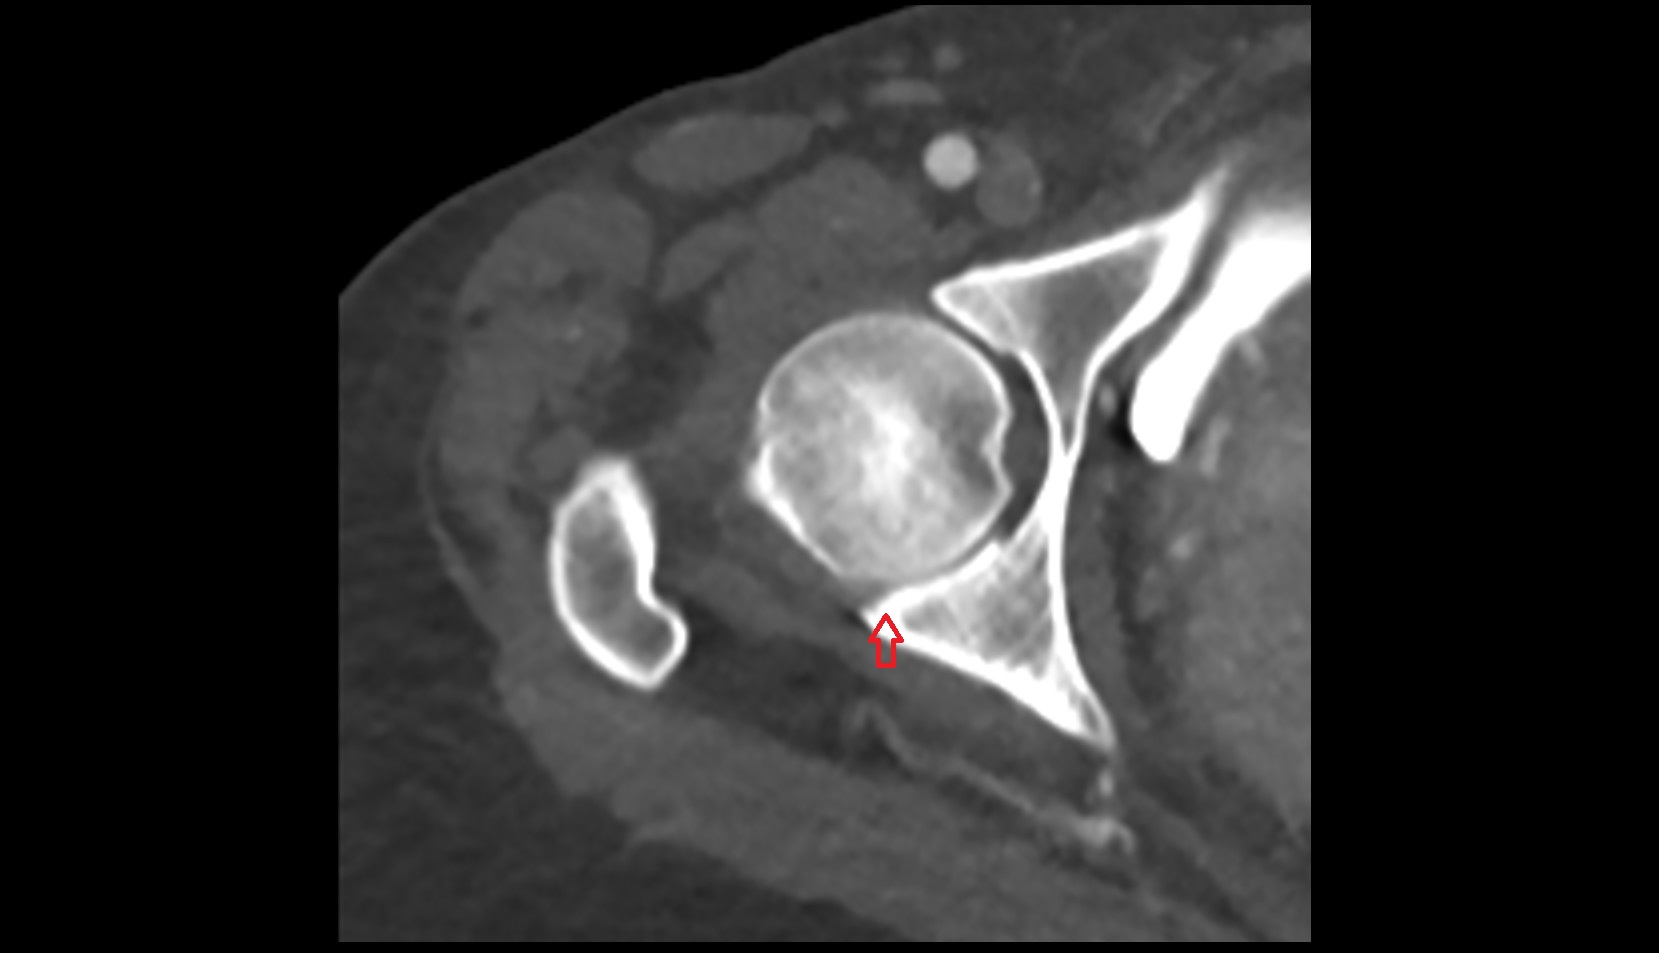

- Head of femur

- Acetabular labrum

- Hip joint